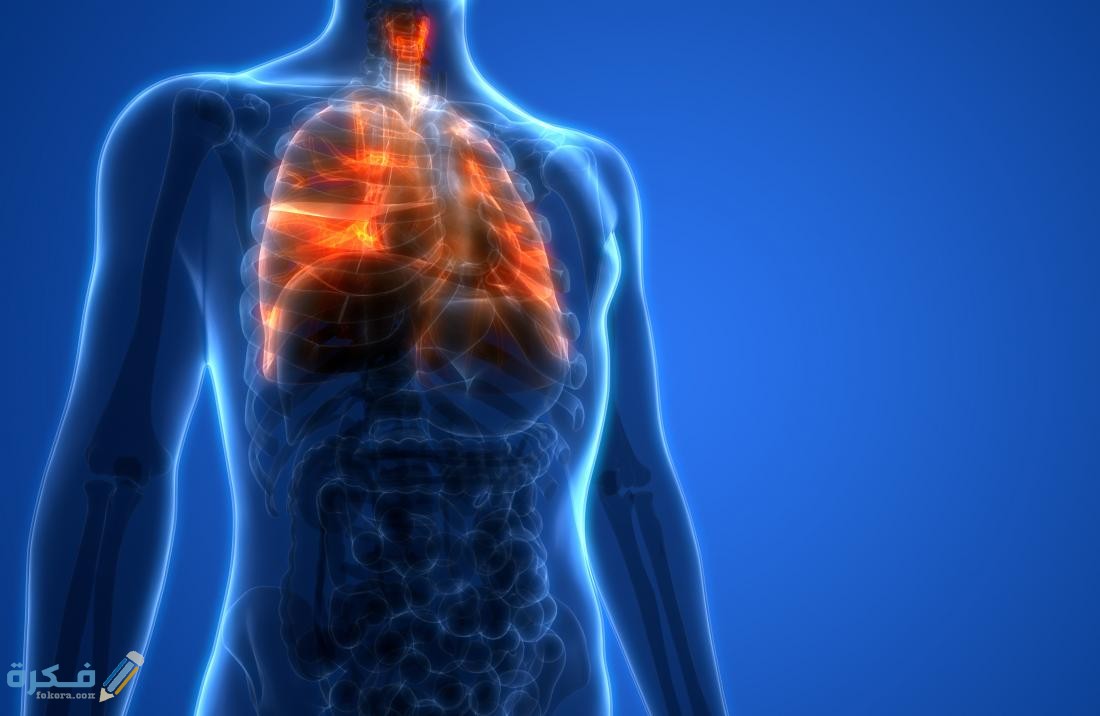

أكمل القراءة »علاج التهاب القصبة الهوائية بالعسل و 3 أعشاب طبيعية من خلال موقع فكرة يعد التهاب القصبة الهوائية واحد من الأمراض…